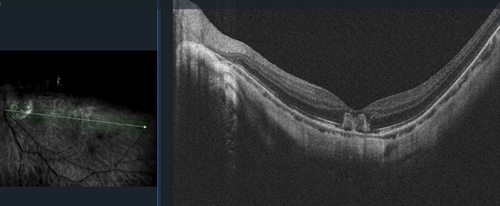

Anterior examination showed clear cornea and posterior subcapsular cataract OU. Dilated fundus examination demonstrated posterior vitreous detachment of the right eye and macular hemorrhage in the left eye. Optic nerves appeared pink and sharp, and the vessels appeared normal. Optical coherence tomography revealed mild irregular foveal contour OD and subretinal choroidal hyperreflective lesion OS.

OCT of the left eye showing a subretinal choroidal hyperreflective lesion. |